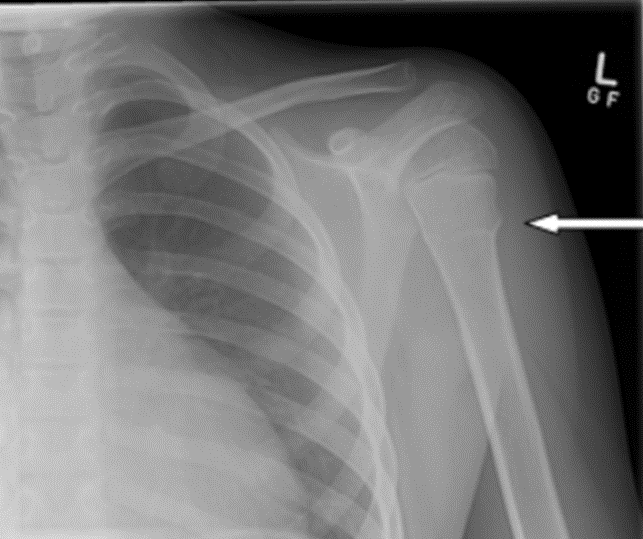

Your child has sustained a break (fracture) to the proximal humerus which is the arm bone close to the shoulder and the doctor has confirmed this.

Your doctor has reviewed your child’s x-rays today and confirmed this fracture is simple and undisplaced.